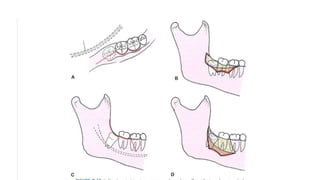

• Mesioangular impaction:

-section the distal part from the tooth and remove it

-followed by the mesial portion

• Horizontal impaction:

The distal portion of the crown is sectioned first then the distal part of

the root, followed by the mesial portion of the tooth

• Vertical impaction

- The tooth is sectioned into mesial and distal .

- Mesial half is removed followed by the distal half

• Distoangular impaction

- The crown of the tooth is removed first, followed by either of the

roots